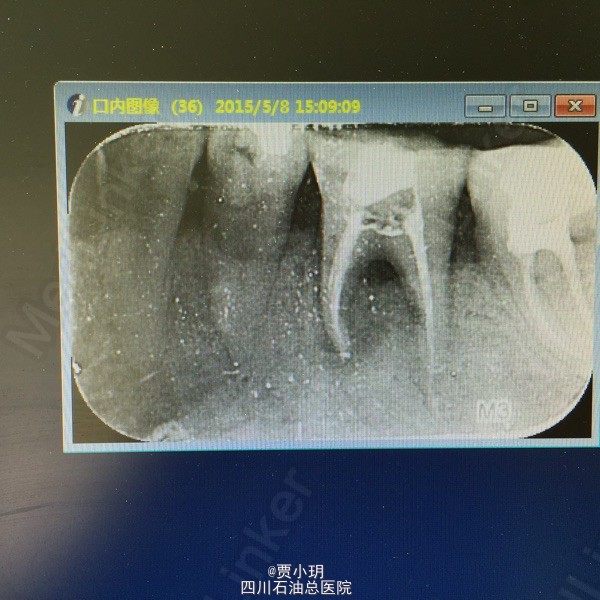

诊断:36牙周牙髓联合病变 处理:1、局麻下,行36开髓,封失活剂。同期行36牙周治疗,包括牙周洁治,根面平整,双氧水反复冲洗并上药。 2、一周后复诊,36常规行根管治疗,行MTWO根扩。 3、一周后复诊,36再次行牙周刮治,冲洗,上药。 4、一周后复诊,36行根充,复合树脂充填。观察随访,择期行牙冠修复。

随访:患者根充后一个月复诊,未有任何不适,查体可见36松动I度-,叩痛(-),颊侧牙龈略有退缩。X线示36根周阴影范围明显缩小,骨密度有所增加。拟三个月后复诊。 今日患者根充后四个月复诊,拍片可见根周和根分叉的炎症已经明显控制,骨密度良好,但是根分叉的骨吸收还是存在。且患者目前无任何临床不适,查体见36松动度(-),根分叉探及无牙周袋,牙龈附着良好。 讨论:其实刚开始对这颗牙的治疗没抱太大希望,因为初诊情况太差,但该患者保留意愿很强烈,而且配合度很好。而且以前没有尝试过牙周方面的治疗。其实如果牙周治疗方面能更严谨和完善,可能效果会更好,比如对颊侧牙龈附着的恢复和骨再生。下面是每次治疗的对比图。